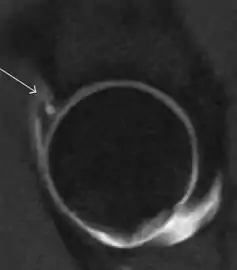

Axial CT image of pigmented villonodular synovitis eroding the posterior cortex of the femoral neck.[1]

Sagittal T2* gradient echo image showing a posterior soft tissue mass with hypointense areas secondary to hemosiderin deposition.[1]

In synovial proliferative disorders, MRI demonstrates synovial hypertrophy. In the case of PVNS, characteristic foci of low signal intensity related to hemosiderin deposition are better seen on gradient echo T2* images (Figure 7). In the case of synovial osteochondromatosis, the synovial hypertrophy is accompanied by intermediate signal cartilaginous loose bodies and/or low signal calcified loose bodies.[1]